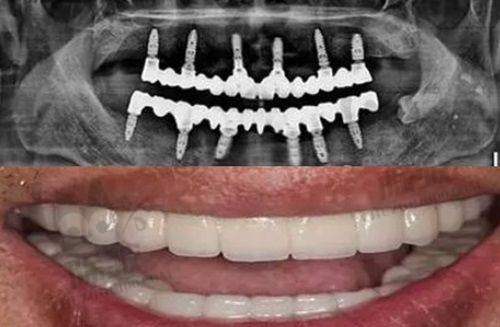

特色项目:种植牙和矫正牙齿是其特色项目。采用3D导航种植牙技术,在复杂的全口种植、all - on - 4种植等手术方面经验多。

特色项目:种植牙和正畸是主打项目,在整牙种牙过程中会结合口腔美学标准以及个人的口腔、牙齿形态来进行方案设计,能处理全口牙缺失的种植。

医院优势:是广西本地创办的医院,尤其在重度缺牙者的种植修复方面精细度高,是疑难种植牙专科。

特色项目:擅长疑难种植牙,在常见的洁牙、补牙以及复杂的种植牙手术等方面都能提供个性化治疗方案。

特色项目:擅长数字种植牙和青少年早期矫治。